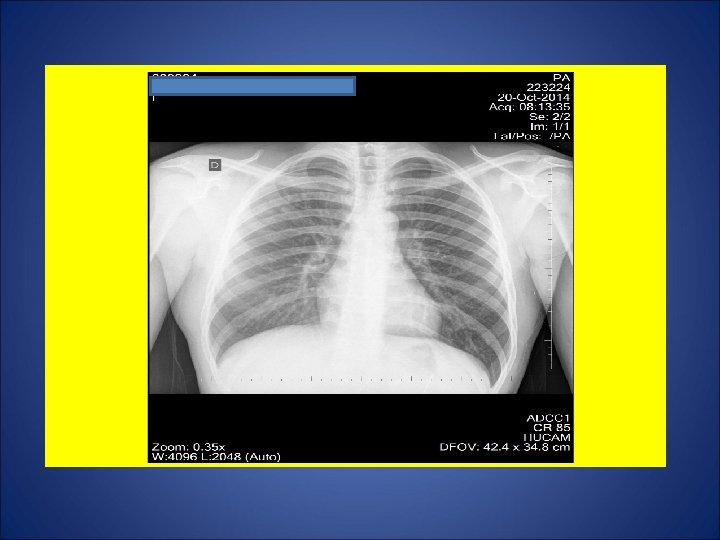

CASO 2, feminina, 37 anos de idade, auxiliar de serviços gerais, natural de Governador Valadares, residente em Cariacica (ES). Por volta de 04 Out 14, procurou P. A. devido a tosse não produtiva, febre, sudorese, calafrios, cefaléia e diarréia há 2 semanas. Foram prescritos algumas medicações (incluido antimicrobiano). Relatou perda de 4 Kg e hiporexia durante as últimas 3 semanas. Remissão da febre, sudorese e calafrios há 1 semana. Em 11 Out, procurou de novo o P. A. devido à ausência de melhora clínica. Foi internada devido ao diagnóstico de derrame pleural à direita, sendo iniciados ceftriaxone 2 g/dia e oxacilina 1 g E. V. 4/4 h. Em 15 out, foi transferida para a enfermaria de Pneumologia do Hospital Universitário para propedêutica de derrame pleural. Negou Tuberculose prévia. Contato intra-domiciliar (mesma cômodo e mesma cama) durante os últimos 14 anos com seu marido em tratamento para tuberculose pulmonar (5º mês). Tabagista e etilista. Dependência química prévia por 1 ano (maconha, cocaína e crack). HIV negativa. Ex. físico: Estado geral regular, P=61 Kg, Alt=1, 68 m, IMC= 21, 6 Kg/m 2. Propedêutica respiratória compatível com derrame pleural.

ESCARROS INDUZIDOS: 1º) 17/10/14: 1 m. L – MUCÓIDE – 55 min: BAC NEG – CULT em curso 2º) 20/10/14: 10 m. L – SALIVA – 40 min: BAC NEG - CULT em curso 3º) 21/10/14: 6 m. L – SALIVA – 46 min: BAC NEG – CULT em curso 4º) 22/10/14: 11 m. L – SALIVA – 50 min: BAC NEG – CULT em curso 5º) 23/10/14: 10 m. L – MUCÓIDE – 1: 10 min: BAC NEG – TRM: M. tuberculosis DETECTADO – CULT EM CURSO